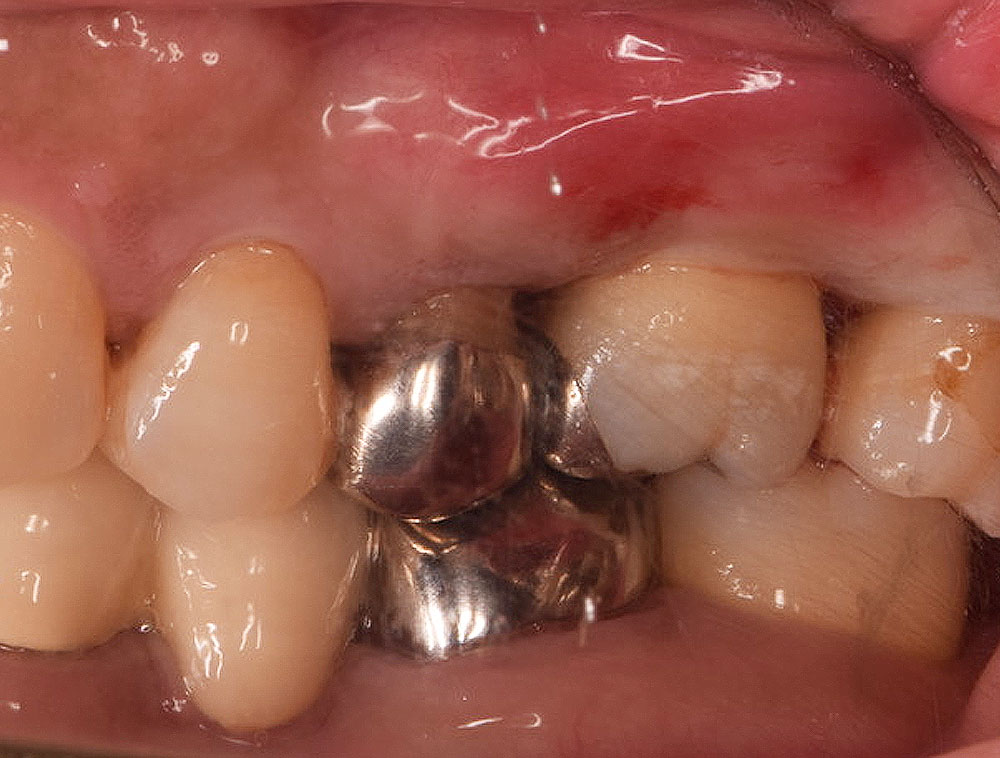

患者さんは40代の女性で、歯がグラグラで噛めないので噛めるようしたいと恵比寿・広尾歯科に来院されました。お口のなかを拝見すると歯周病が進行し特に奥歯の歯周ポケットが深くなり、歯を支える顎の骨が溶けている状況でした。歯ブラシで磨きにくいため汚れが溜まりやすいだけでなく、奥歯は噛み合わせの力が強く加わり歯周病の悪化しやすい歯です。この患者さんも以前、保険の銀歯で治療されていましたが、年々歯がグラグラ(動揺)して噛めないとご来院されました。